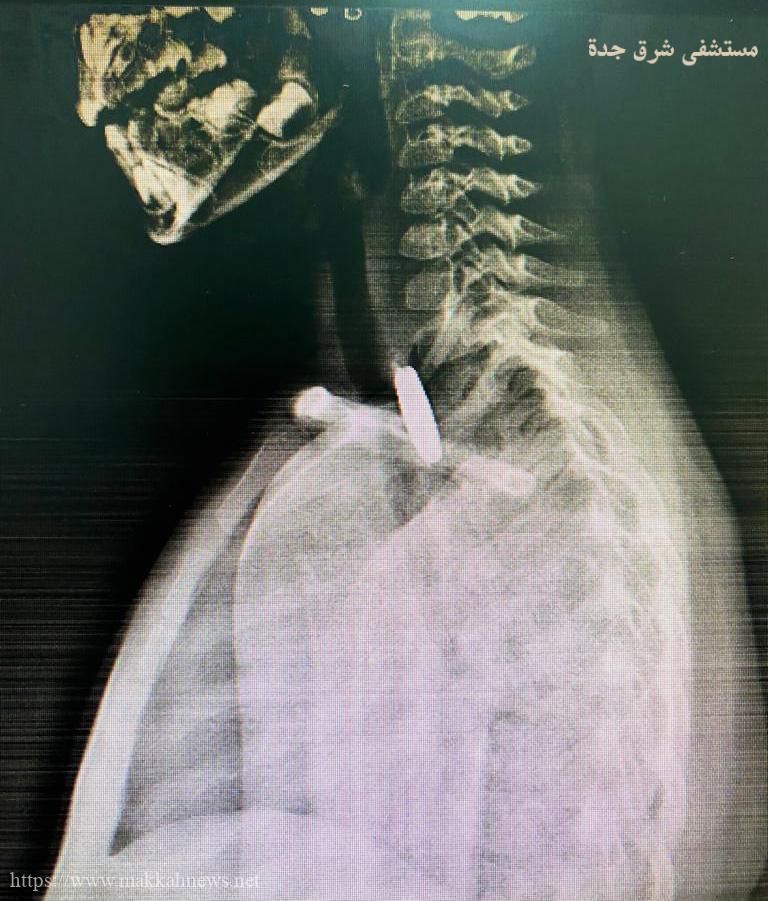

عملية دقيقة تنجح في إنقاذ طفلة بعمر ثلاث سنوات بمستشفى شرق جدة

(مكة) فوزية الفواز _ الرياض _ نجح فريق طبي إستشاري بقسم الأنف و الأذن و الحنجرة و جراحة أورام الرأس…